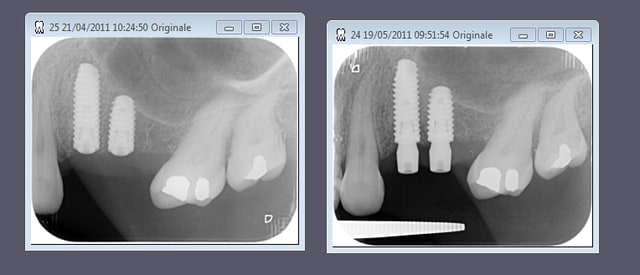

deux axiom en 24 25

dans l'ordre

avulsion des dents et j'ai tracté tout le vestibule en palatin et suturé sur le bord palatin sans membrane sans matériau de comblement

pose de deux axiom en 14 15 mais... plus de GA en vestibulaire puisque tout est sur la crête

à la mise des vis de cicat incision palatine en 1/2 épaisseur puis pleine épaisseur sur le bord vestibulaire de la crête et décharge mésiale et distale et on redéplace tout en vestibulaire petites incision (à la chez plus ki) et sutures.

pas mécontent du modelage en vestibulaire et de la "papille" interimplantaire. on verra à la maturation ce que ça devient.

au passage amusant de voir que si on se contente de regarder les radios n se dit fouilla t'était bourré le jour de la pose t'es à des kilomètres de la 6 (en fait 7 mésialée)

je suis pas satisfait de ma décharge mésiale noah je sais...